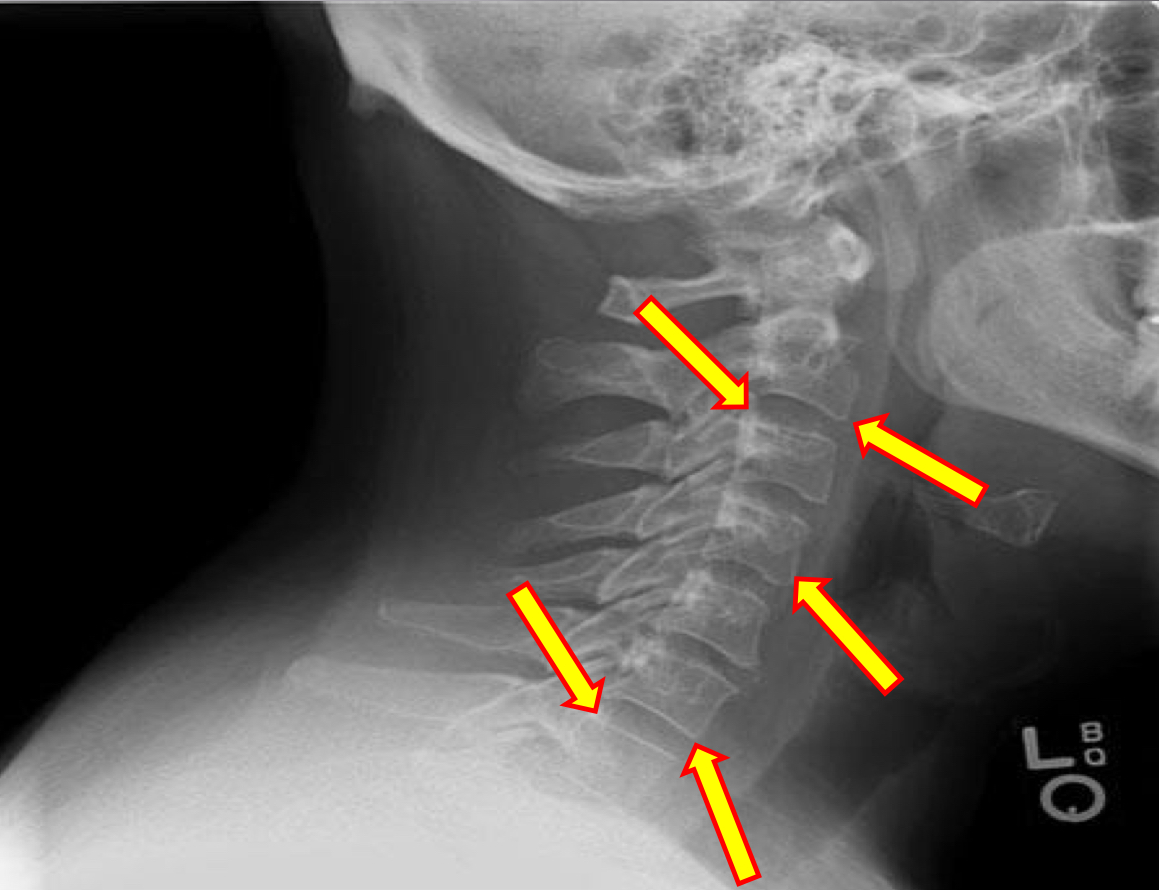

What view is this?

Lateral Cervical

What is this?

Mandible

What is this?

Hyoid bone

What is this?

Mitchel Marker

What is this?

Occipital Condyle

What is this?

C1 Anterior Tubercle

What is this?

C1 Posterior Arch

What is this?

Odontoid Process

What is this?

Atlanto-Dental Interspace